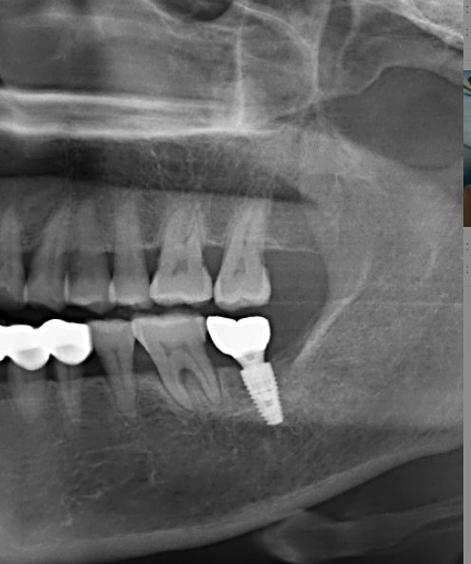

- 口腔CBCT: 这是种植前必须的检查设备,用于精确评估骨量、神经血管位置等。没有CBCT的机构,种植风险较高,建议谨慎选择。